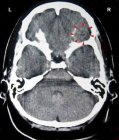

DEVELOPMENT AND FUNCTION OF THE MOUTH AND PHARYNX SUBMUCOSA: The mouth is the opening of the alimentary canal and the place where the digestion (secretory quality) and absorption (absorptive quality) of food starts. The tongue is an accessory digestive organ that aids in chewing and swallowing. Through chewing, food is broken into small pieces. Saliva produced in the salivary glands moistens the food bolus to make swallowing easier. The salivary glands are located in several parts of the mouth. The largest salivary glands are the parotid glands in front of the ears, the sublingual glands underneath the tongue, and the submandibular glands beneath the lower jaw. The pharynx connects the mouth and nasal cavities with the trachea and the larynx. The nasopharynx, located in the back of the nose, extends to the upper surface of the palate which forms the roof of the mouth; the oropharynx is at the very back of the mouth. On both sides of the pharynx lie the tonsils. Branching off the pharynx is the esophagus that carries food from the mouth to the stomach. The submucosa of the mouth and pharynx (including the lips, gums, palate, tongue, salivary glands, tonsils, and throat) consists of intestinal cylinder epithelium, originates from the endoderm and is therefore controlled from the brainstem.

CONFLICT-ACTIVE PHASE: Starting with the DHS, during the conflict-active phase cells in the submucosa of the mouth or pharynx proliferate proportionally to the intensity of the conflict. The biological purpose of the additional cells is to better insalivate a morsel in order to absorb (right half) or expel (left half) it faster. Salivation is stimulated by the autonomic nervous system. This is why the secretion of saliva increases with the smell of “mouth-watering” food. In the English language, “salivating” and “drooling” are synonyms for “craving” for something or someone desirable.

With prolonged conflict activity a flat growth (absorptive type) develops in the submucosa of the mouth. In the palate, salivary glands, tonsils, pharynx, and throat it can also take a cauliflower-shaped form (secretory type). If the papillae of the tongue that contain the taste buds are affected, the additional cells provide an enhanced sense of taste in order to be able to analyze (see sensory quality) the “morsel” (compare with hypersensitivity to taste related to the posterior third of the tongue).

Adenoids in the nasopharynx form as a result of a hanging conflict, that is, when the “scent morsel”-conflict cannot be resolved in time (compare with polyps in the paranasal sinuses). If the tonsils are affected, this causes tonsillar hypertrophy, or enlarged tonsils. Since the tonsils and the nasopharynx share the same brain relay, nasal polyps and enlarged tonsils often occur together.